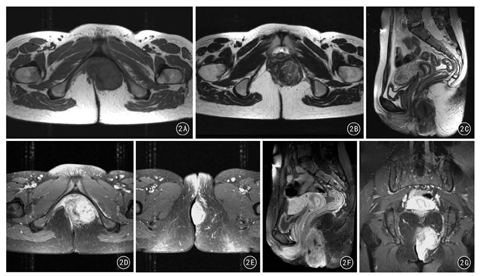

患者女,23岁,2015年1月发现肛周左侧臀部皮下肿物,伴间断胀痛,无发热、恶心、呕吐、腹痛、腹泻等症状,无便血,自以为"痔疮",就诊于当地医院,临床诊断"痔疮合并感染"予以抗感染治疗,肛周疼痛症状缓解,但肿物未见缩小。2015年6月再次出现肛周胀痛,遂二次就诊初诊医院,并以"肛周脓肿、肛瘘"行肛周肿物切除术,术中发现肿物为肛周皮下并累及深部实性软组织肿瘤,未予切除,建议至上级医院进一步治疗。2015年6月16日,患者就诊于山西省肿瘤医院,以"肛周肿物"收住院。患者自发病以来精神、食欲、睡眠可,大、小便正常,无明显消瘦。入院后行血常规、尿常规、凝血5项、肝肾功能、乙肝系列、人类免疫缺陷病毒等实验室检查,结果均无异常。经直肠超声检查提示肛门左侧皮肤及皮下软组织内实性不均质低回声病变,形态欠规则,边界较清,见低回声纤维包膜;彩色多普勒血流显像(color Doppler flow imaging, CDFI)检测见丰富血流信号(图1)。MRI提示:肛门左侧皮肤及皮下深部软组织内见软组织信号影,范围约5.3 cm×4.1 cm ×4.0 cm,信号不均匀,T1WI与肌肉呈等信号,T2WI呈中、高混杂信号,病变内见点状、小灶状低信号区,DWI呈不均匀等信号,注射对比剂钆喷酸葡胺注射液增强扫描呈明显强化,强化区域似呈条带状、旋涡状强化,病变内点状及灶状低信号区未见强化(图2)。患者于2015年6月22日在全身麻醉下行臀部肛周肿物切除术。术中见肿物位于肛门左后方3 cm处,皮肤表面可触及的肿瘤直径约4 cm,色白、质硬。沿肿物边缘切开皮肤,仔细分离肿物与周围组织粘连,避免损伤肛门括约肌及直肠,完整游离肿物,切除标本送病理检查。大体标本见:附皮肤软组织一块,大小6 cm×5 cm×4 cm,皮肤大小5.5 cm×4.5 cm;皮肤表面可见一隆起,范围4.5 cm×4 cm,肿物切面灰白、质韧。术后病理检查提示:镜下瘤细胞呈梭形,围绕血管呈束状、结节状排列;免疫组织化学检测:AE1/AE3阴性,Vimentin阳性,S-100阴性,平滑肌肌动蛋白阳性,CD34阳性,Ki67约2%,β-catenin阳性。病理诊断:血管平滑肌瘤(图3、图4)。

MRI软组织分辨率高、多方位成像对显示软组织肿瘤具有较大优势。MRI图像上,CAL多表现为T1WI低信号,T2WI为高信号病变内夹杂斑点状、小灶状均匀或混杂低信号。一般认为高信号代表血管和平滑肌细胞成分,低信号代表血管内血栓、泥沙样或斑点状钙化。病灶内部的平滑肌和血管的比例多少,是否伴发出血、血栓及钙化,是MRI信号的病理基础。本例DWI亦呈中等信号强度,可能与肿瘤细胞密度相对较小、细胞外间隙较大,对水分子限制较小,导致水分子弥散增高有关;注射钆喷酸葡胺后,T2WI高信号区域呈持续性明显、漩涡状强化,可能与肿瘤血管和固有平滑肌排列形态有关;另外,注射钆喷酸葡胺后增强扫描,肿瘤明显强化再次印证了CAL为富血供肿瘤。CAL的纤维性假包膜在T1WI、T2WI呈低信号,增强扫描强化不明显。MRI对显示漩涡状强化结构较敏感,对诊断CAL具有一定特异性[13,14]。